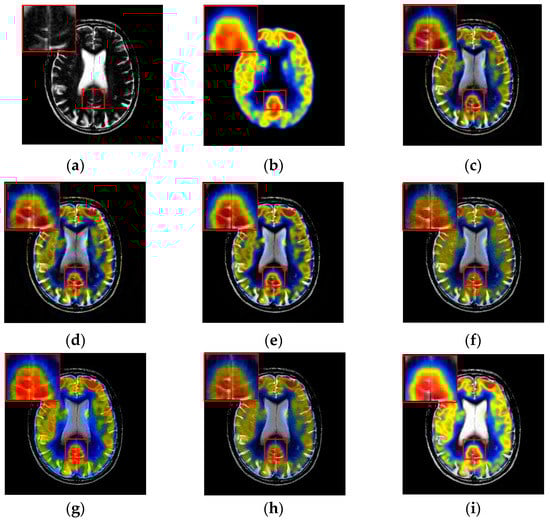

To further demonstrate that the proposed method is equally effective for other types of medical image fusion, we test the other two categories of medical image fusion systems include MRI/SPECT and MRI/PET, and the fusion results are shown in Figure 9 and Figure 10. The details of fused images are zoomed in and presented in the bottom left corners of their respective images.

Figure 9.

Fused results of MRI/SPECT medical images by different methods. (a) MRI; (b) SPECT; (c) DCTWT; (d) Curvelet; (e) NSCT; (f) Liu-ASR; (g) Kim; (h) Zhu; (i) Proposed.

Figure 10.

Fused results of MRI/PET medical images by different methods. (a) MRI; (b) PET; (c) DCTWT; (d) Curvelet; (e) NSCT; (f) Liu-ASR; (g) Kim; (h) Zhu; (i) Proposed.

With more careful observation, we can see that the spatial edge details and brightness information in Figure 9i and Figure 10i are more accurate compared with Figure 9c–h and Figure 10c–h generated by the six compared methods. This means the useful information from source images have been successfully transformed into the fused images, that is, our fused results have the best visual features. This is mainly because the novel construction of the overcomplete dictionary in this paper is composed of two parts include the brightness sub-dictionary and the edge detail sub-dictionary, which can fully express the significant features of the medical images. This will be very beneficial to the implementation of medical image fusion in practical medical assistance applications. In conclusion, the proposed algorithm has the best subjective visual effect.